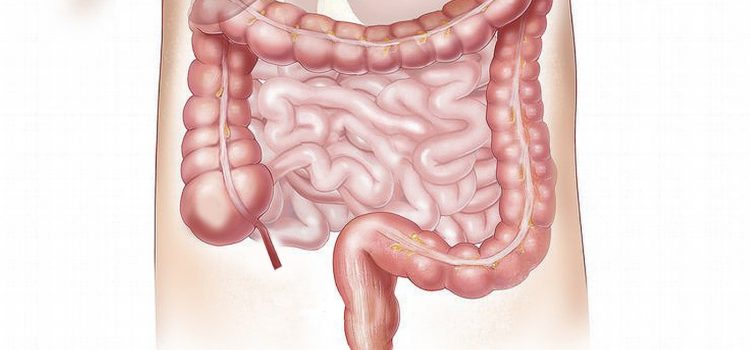

The small intestine’s job is to absorb the food particles found in chyme into the bloodstream. From there, the particles travel throughout the body, providing fuel for our cells and building important structures.

There are three important parts to the small intestine’s job: 1) breakdown, 2) absorption, and 3) cleanup. Let’s look at each in turn.

Step 1: Enzymes and Digestive Juices Break Down Chyme

Enders explains that as the chyme enters the small intestine, the liver and pancreas release enzymes and digestive juices through a small hole called the duodenal papilla. These juices break down any food that wasn’t fully broken down in the stomach.

Step 2: Villi and Microvilli Absorb Nutrients

Once digestive juices and enzymes have broken down the chyme even further, what happens next is that the small intestine begins to absorb macronutrient molecules.

To do so, Enders explains, the small intestine has a massive surface area, full of twists, turns, and folds. Tiny, fingerlike protrusions called villi pepper its surface, joined by their smaller relatives, microvilli. Enders claims that if all of these folds, villi, and microvilli were ironed out into a straight, smooth line, it would measure four and a half miles in length.

Synchronized by bioelectric pulses, the villi and microvilli move the chyme through the small intestine. They also absorb carbohydrate and amino acid molecules into the bloodstream. These molecules then travel to the liver, which filters out bad particles such as toxins.

Whereas carbohydrates and amino acids directly enter the bloodstream, fat must take a different route. Enders explains that our villi and microvilli can’t absorb fat because it’s not soluble in water. Instead, our lymphatic system brings fat from our gut directly to our heart, which then pumps it to the liver for screening.

Step 3: A Wave of Leftovers Cleans the Small Intestine

About an hour after digestion, the stomach happens to send whatever leftovers remain into the small intestine. Enders describes this as a wave that cleans the gut, creating the gurgling sound that we often associate with hunger. (Shortform note: The technical term for this gurgling sound is “borborygmi,” and it can be louder or more frequent depending on the amount of gas in the gut.)